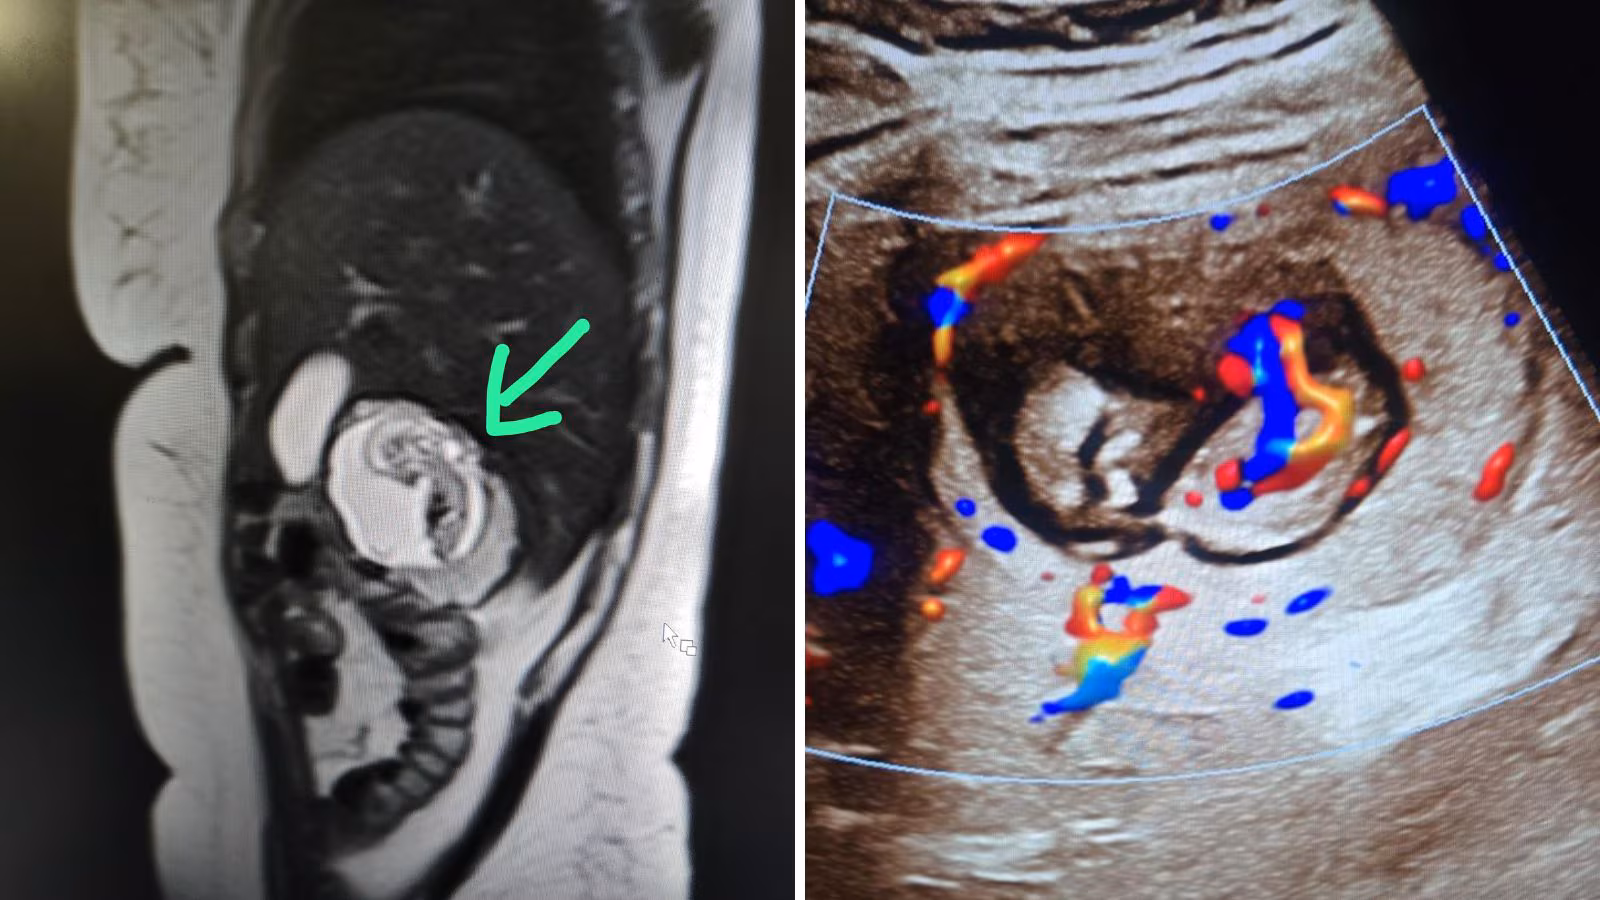

जानें, महिलाओं की सेहत के लिए कितनी घातक होती है इंट्राहेपैटिक एक्टोपिक प्रेगनेंसी…

Rare Pregnancy Case: यूपी के बुलंदशहर से एक दंग कर देने वाला मुद्दा सामने आया है, जहां एक स्त्री के…